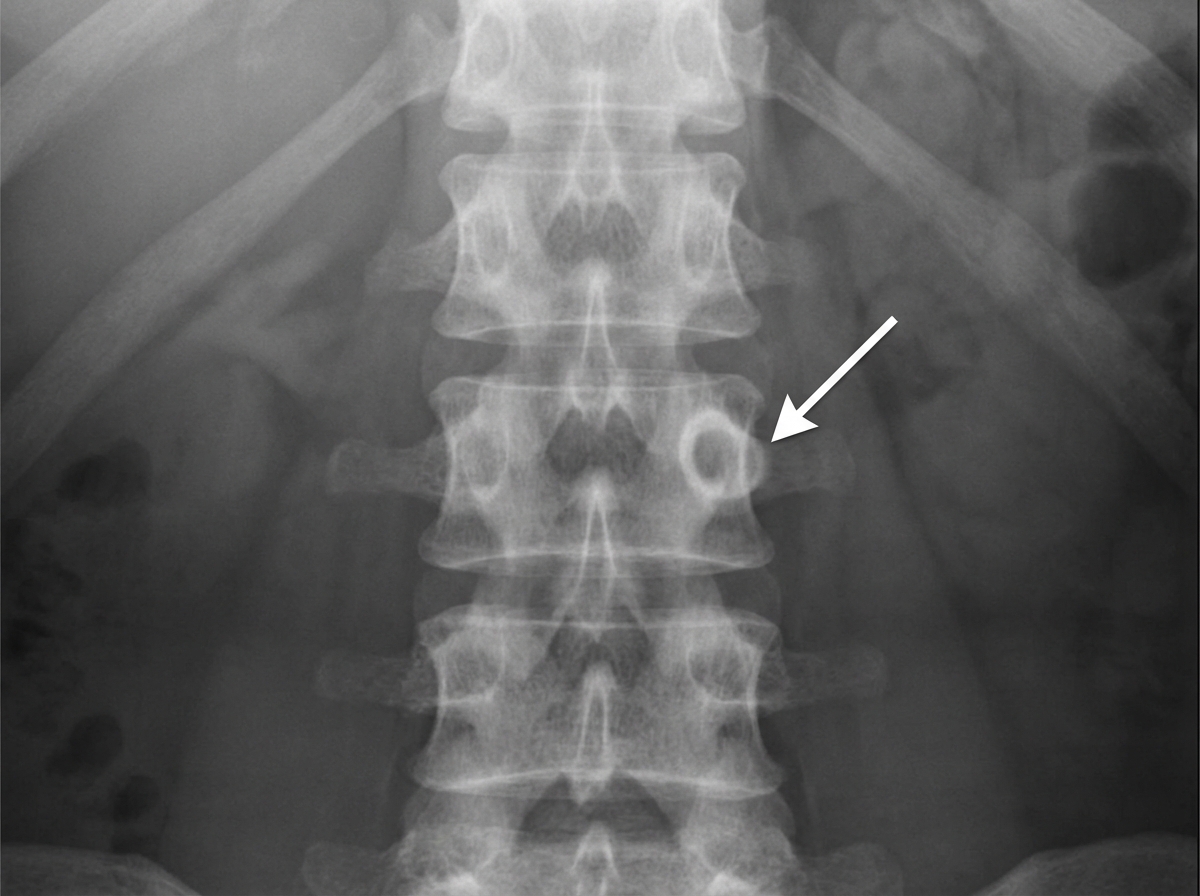

In the provided X-ray, what anatomical structure is indicated by the marked region?

Explanation: ***Pedicle*** - The **pedicle** appears as the **"owl-eye" sign** on AP spinal X-rays, representing the rounded shadow projections from each vertebral body. - Pedicles connect the **vertebral body** to the **posterior elements** and are clearly visible as bilateral circular shadows on anteroposterior views. *Transverse process* - The **transverse process** extends laterally from the vertebra and appears as **wing-like projections** on AP X-rays, not circular shadows. - Located more **laterally** than the pedicles and has a distinct elongated appearance rather than the rounded owl-eye configuration. *Lamina* - The **lamina** forms the **posterior arch** of the vertebra and is not typically visible as distinct circular structures on AP views. - Better visualized on **lateral X-rays** where it forms part of the **posterior spinal canal** boundary. *None of the above* - This option is incorrect as the **pedicle** is clearly the correct anatomical structure being indicated. - The **owl-eye appearance** is pathognomonic for pedicles on AP spinal radiographs.